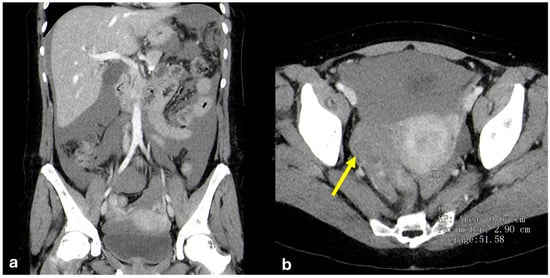

Mesenteric Pseudocyst